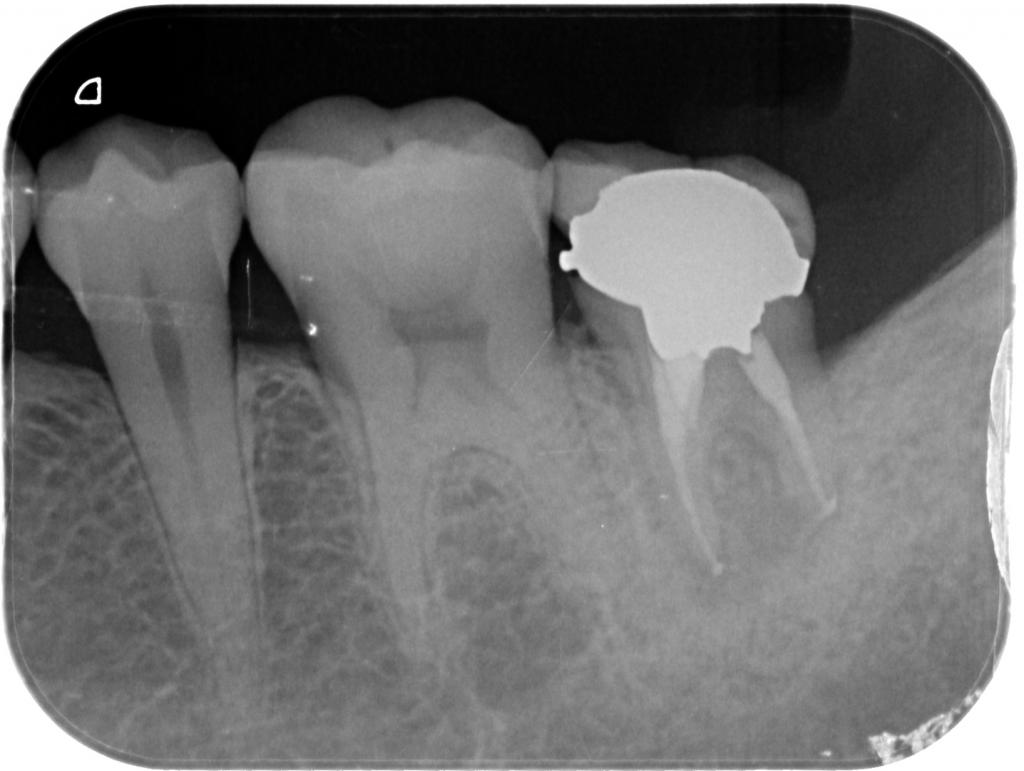

- 術後のレントゲン写真です。

根尖部まで緊密にお薬が充填されていて、歯の周りの骨にも再生が見られました。

動揺も無くなり、以前の様に噛むことができる様になりました。